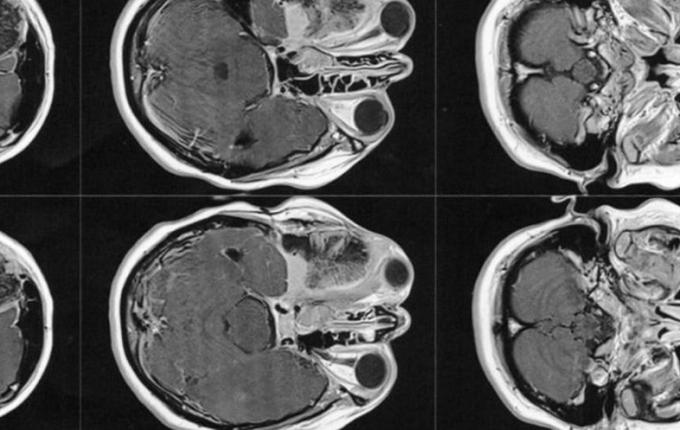

No entanto, mesmo sabendo do diagnóstico, como ela tinha o sonho de se tornar mãe, resolveu engravidar antes de passar pela cirurgia. Porém, durante a gestação, o tumor continuava crescendo, e empurrando o olho para fora. Até que um certo dia, no final da gestação, o tumor empurrou o olho de tal modo que acabou comprimindo o nervo óptico, lhe causando a cegueira do olho direito.

Então este médico solicitou exames de imagem (ressonância magnética e tomografia) para avaliar a situação, os quais foi constatado que o meningioma ainda está ali, e que continua empurrando o olho e se expandindo para outras áreas. Trata-se de um meningioma gigante (medindo 6 x 6,6 x 6 cm), que está localizado na placa do assoalho da fossa média e anterior.

A cirurgia deverá ser feita de urgência, pois o meningioma continua se expandindo, e pode comprimir o olho esquerdo afetando a visão que lhe resta. Também pode comprimir outras partes do cérebro, ou pior ainda, causar a morte.

O médico também disse que será necessário realizar dois procedimentos cirúrgicos, um para retirada do tumor, e o segundo para realocar o olho para seu lugar e implantar a prótese onde o osso foi retirado.